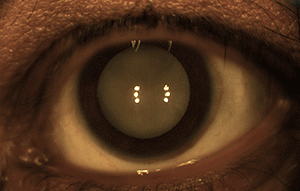

Forus Health’s ophthalmic devices required a variety of optical components including lenses, mirrors, and polarizers. Early versions of their products yielded excellent images at the visible spectrum, yet poor images in the NIR. Bright reflections were evident at the center of the image and interfered with the diagnostic procedure. The visible spectrum allows for normal examination of the entire retina surface and cornea, but high quality NIR images are required for continuous observation without any irritation to the eyes.

Edmund Optics was able to help Forus Health develop prototypes for their ophthalmic devices and support them as they found success and moved to production. Forus Health incorporated standard spherical optical components such as plano-convex and achromatic lenses in conjunction with specialized mirrors and filters. Edmund Optics adjusted the anti-reflection coatings of the components to cover longer wavelengths out to the NIR, which remedied the reflections and noise in the system during NIR imaging. R. J. Venkatramanan, Chief of Manufacturing and QA & RA at Forus Health, stated that "the Edmund technical team helped us to understand the product and improve the quality."

As Forus Health gained traction and scaled up their production, they came out with new models to address different challenges in combatting preventable blindness. The 3nethra classic, Forus Health’s flagship product, is a digital non-mydriatic fundus camera used to quickly capture and transmit images of the eye’s posterior and anterior surfaces. Mydriatic devices dilate the pupil before capturing images. The 3nethra neo differs from the classic in that it is mydriatic, ergonomically designed, lightweight, and hand-held for capturing 120° high-resolution images of the posterior and anterior segments of newborn eyes. The contact device is easily operated by qualified clinicians and can be deployed in versatile clinical environments such as hospitals, operating rooms, and Neonatal Intensive Care Units (NICU).